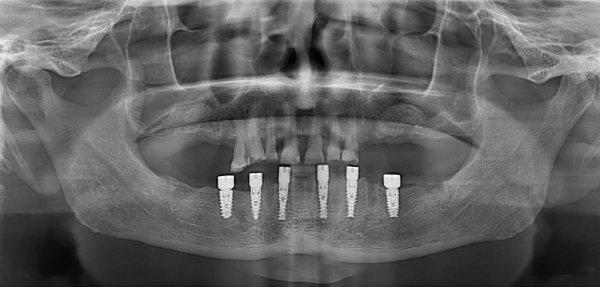

Пациент обратился с просьбой изготовления несъемной конструкции. На нижней челюсти оставшиеся зубы подвижны 2−3 степени из-за пародонтита. Жевательные зубы верхней челюсти так же подвижны и не функциональны.

Первым этапом было выполнено удаление всех зубов нижней челюсти и жевательных зубов верхней челюсти, установка шести имплантатов на нижней челюсти, операция по наращиванию костной ткани на верхней челюсти из-за дефицита костной ткани по высоте (двусторонний открытый синуслифтинг). В день операции пациенту был фиксирован несъемный протез нижней челюсти. Вторым этапом планируется имплантация жевательных зубов верхней челюсти и изготовление несъемных конструкций на них.